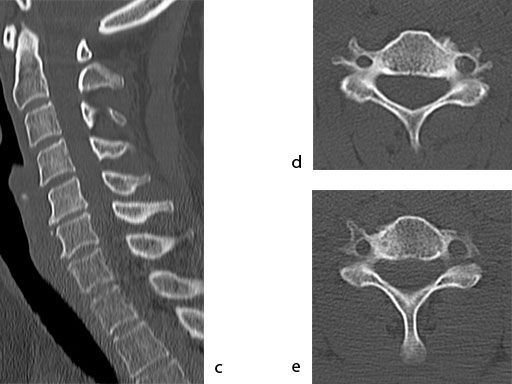

A 51-year-old woman was affected by cervical radiculo-myelopathy due to spinal and neuroforaminal stenosis. The preoperative CT scans are shown at Fig 4 and MRI at Fig 5.

The patient was treated by anterior cervical decompression and fusion (ACDF) with ZERO-P filled with ChronOS. No autologous bone graft was used. Postoperative images are shown (Fig 69).